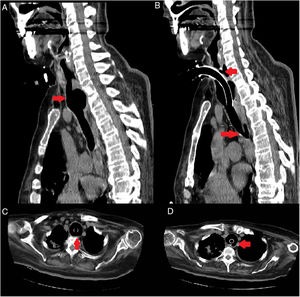

Describimos el caso de una mujer de 67 años diagnosticada de esclerosis lateral amiotrófica desde 2008, con necesidad de alimentación enteral por gastrostomía endoscópica percutánea (PEG) desde 2010 y ventilación mecánica invasiva (VMI) a través de traqueostomía desde 2015. En 2018, tras 3 años con VMI, acude a urgencias por fiebre, objetivándose salida de contenido alimentario a través de la traqueostomía. La tomografía computarizada (TC) de tórax reveló una fístula traqueoesofágica de 5×2,6mm en la región posterolateral izquierda de la tráquea junto con dilatación traqueal en la zona de inserción de la cánula (fig. 1). Aunque se implantó una cánula traqueal para superar el trayecto fistuloso, dada la escasa mejoría clínica y los antecedentes personales, se optó por una limitación del esfuerzo terapéutico.